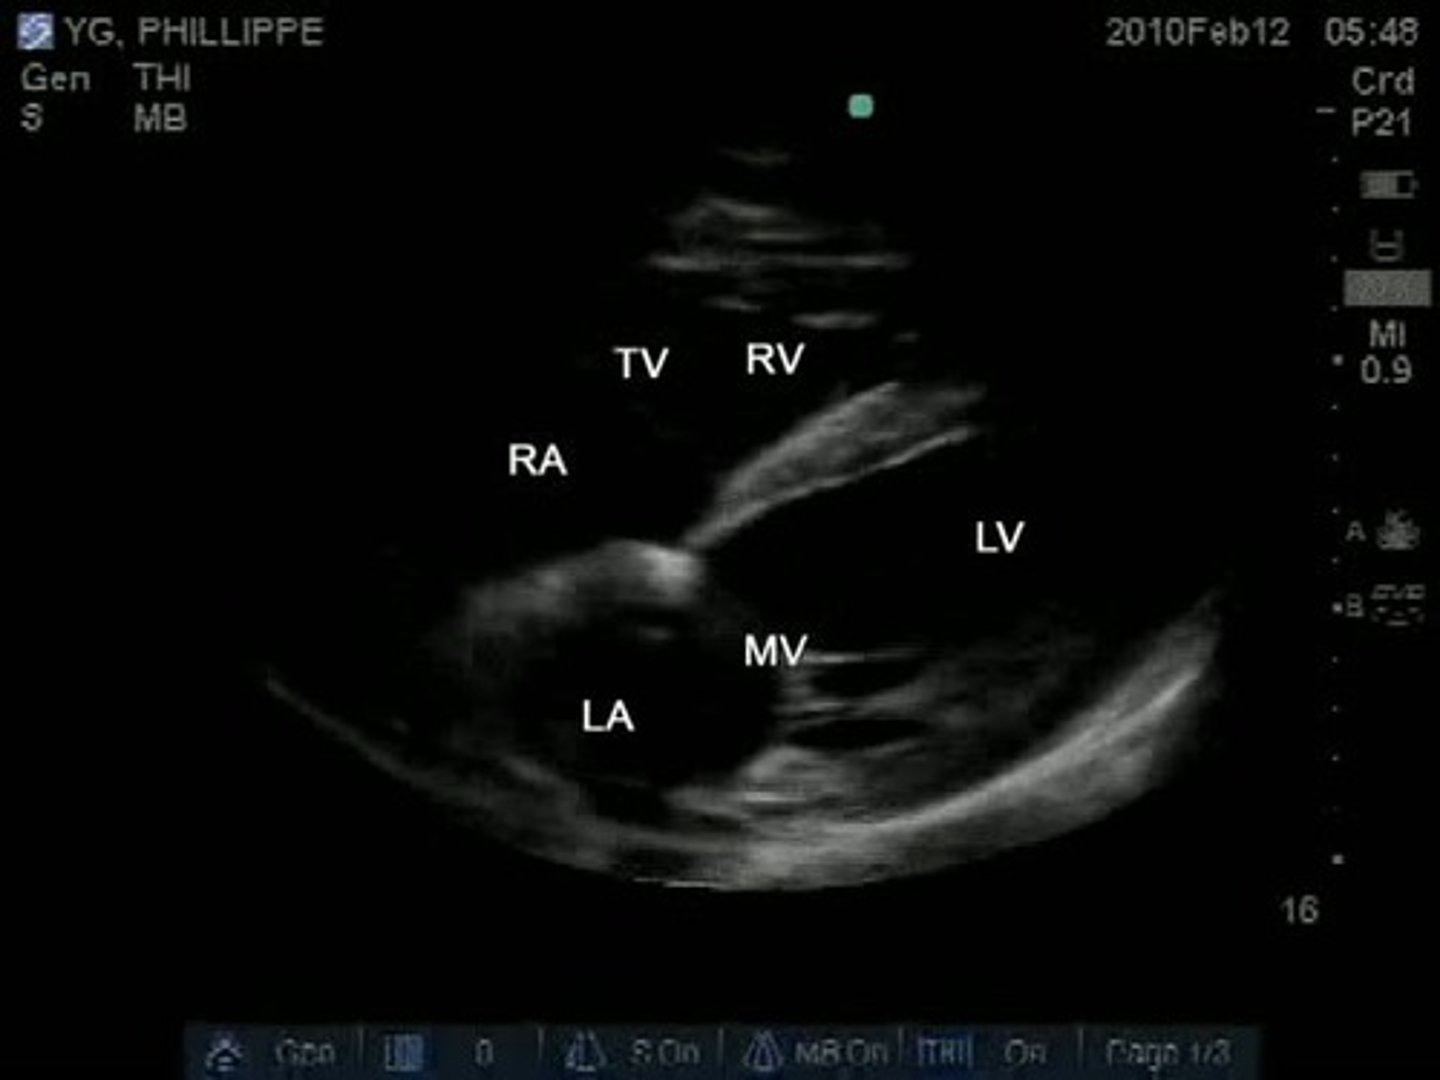

RVIT is used to visualize ____

TV

RVOT is used to visualize _______

PV

PSLA is used to visualize ____ and _____

MV and AoV

A4 is used to visualize _____ and ____

MV, TV

A5 is used to visualize ____, ____, and _____

TV, MV, and AoV

A2 is used to visualize _____

MV

A3 is used to visualize ___ and ____

subcostal 4 is used to visualize _______, ___, ___, ____, and ___

four chambers, TV, MV, IVS, IAS